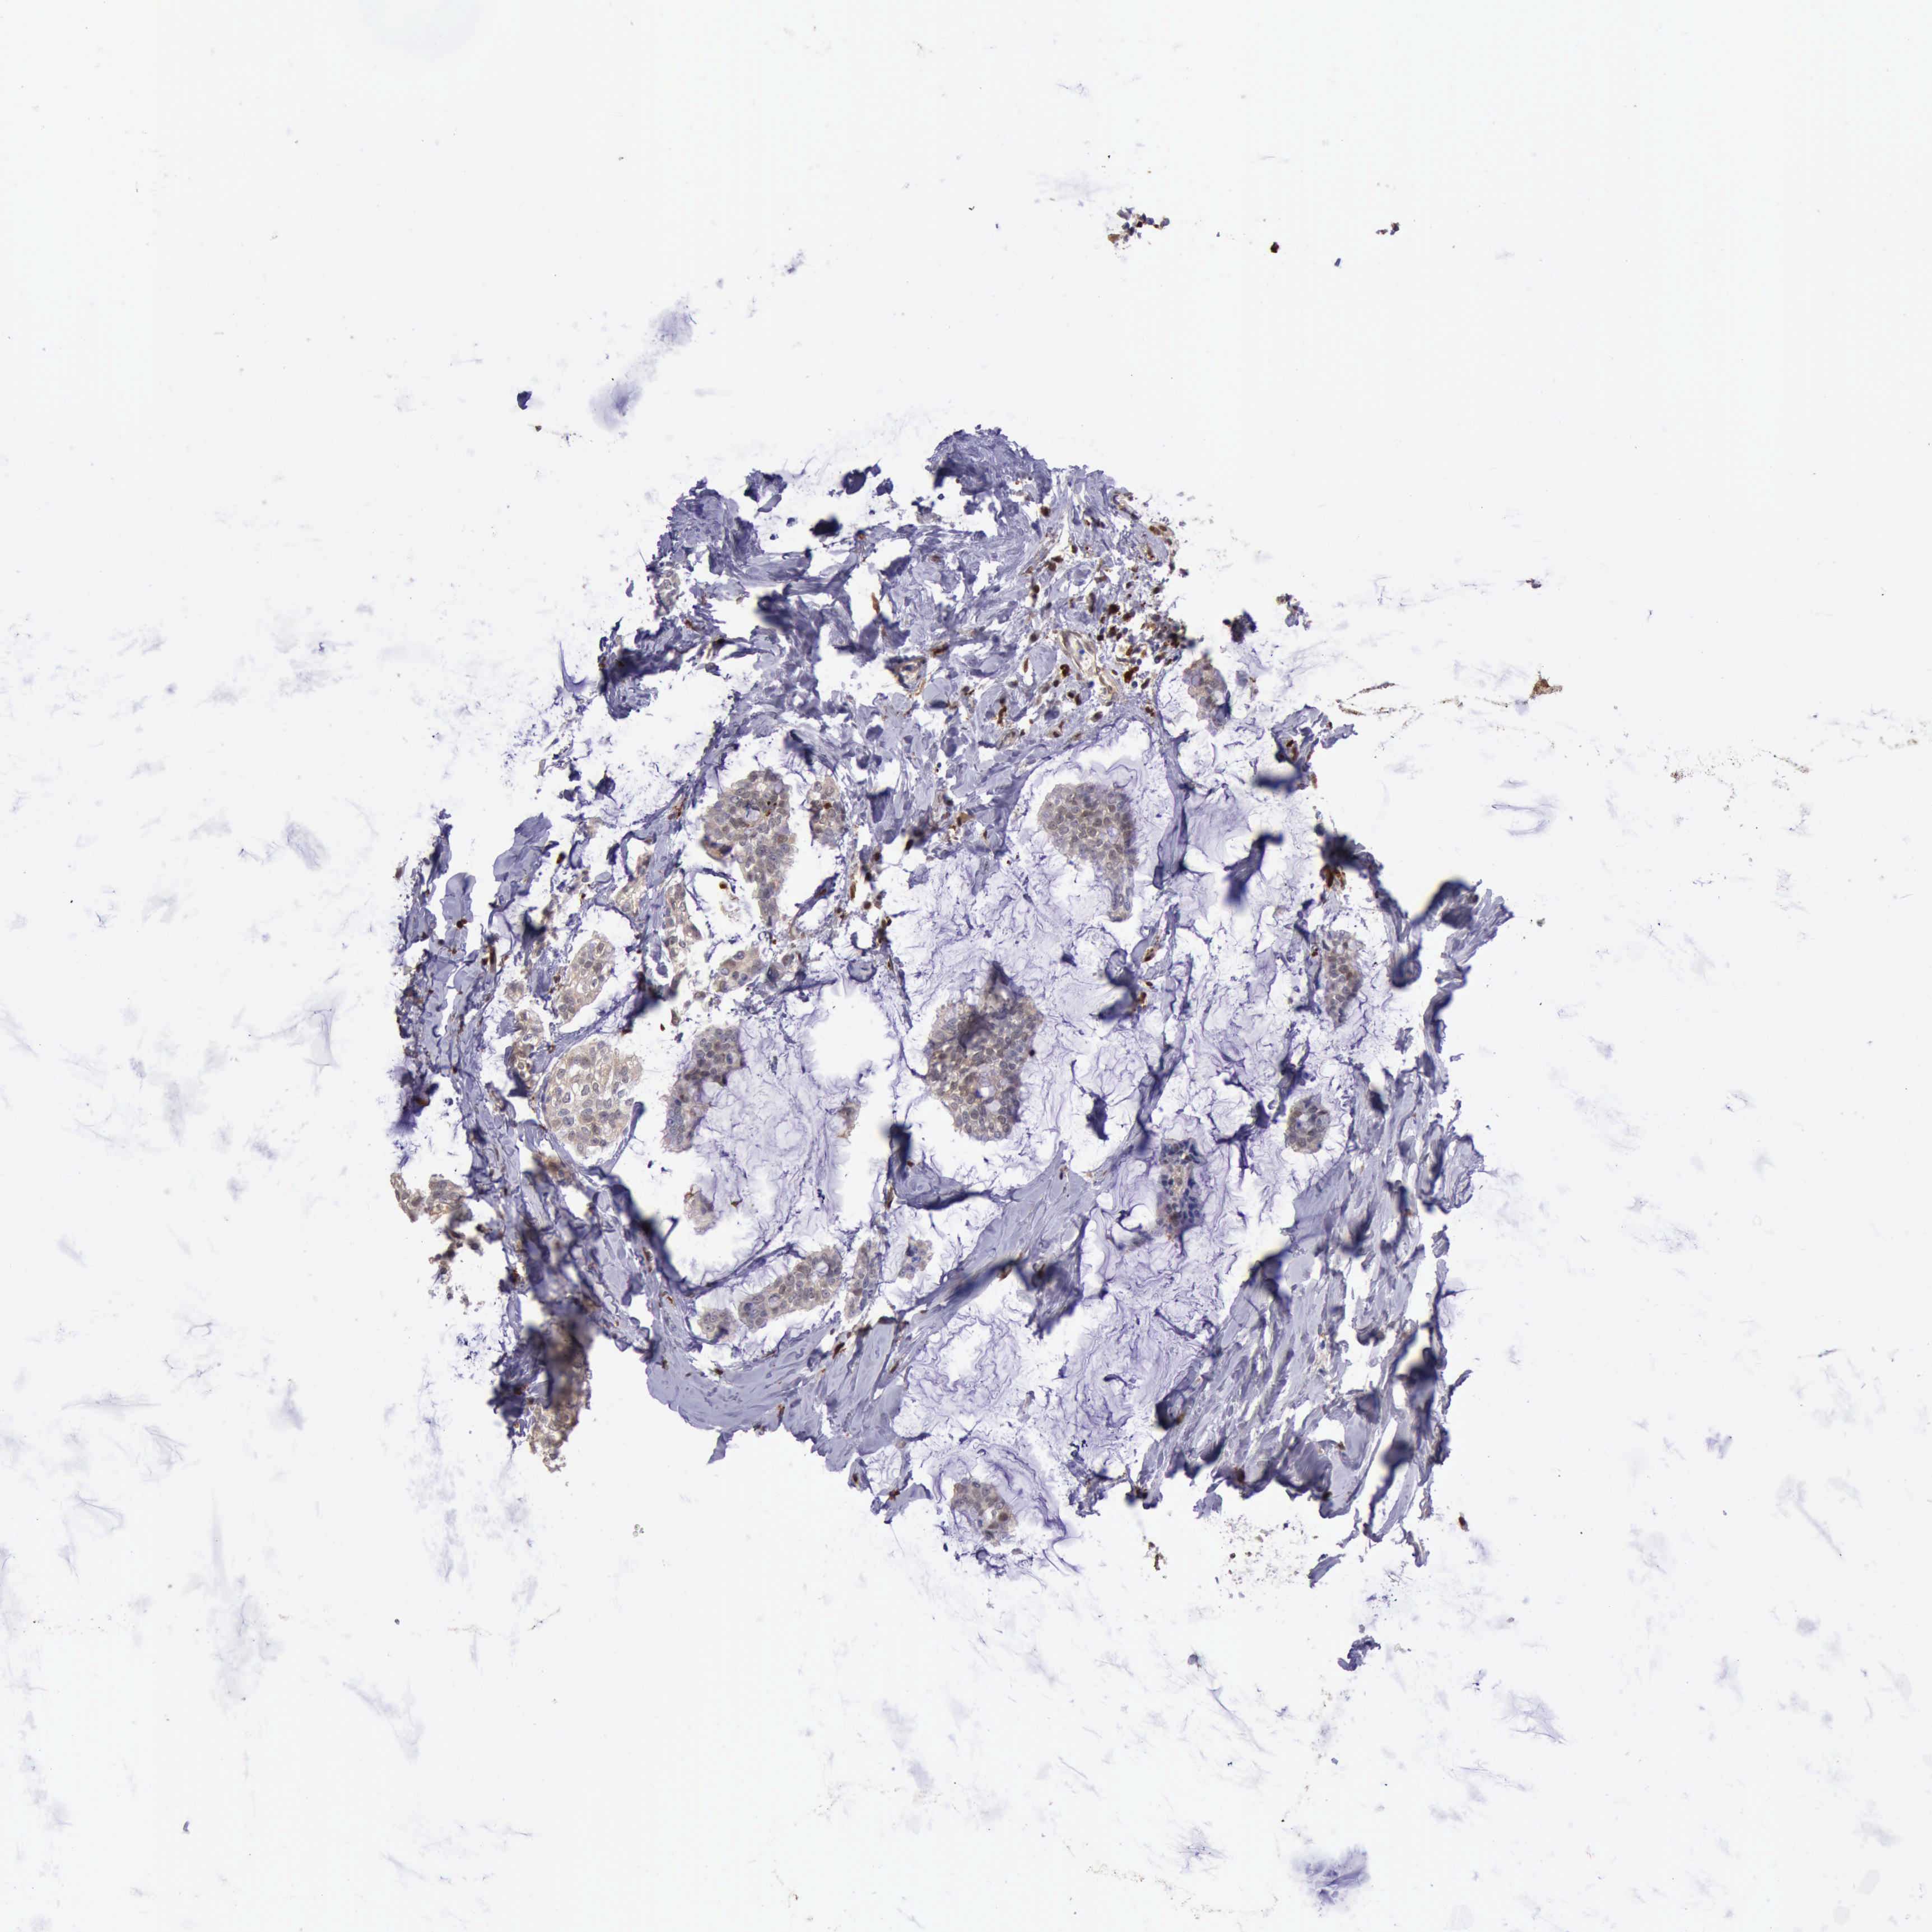

BRCA TCGA BRCA VALIDATION PROTEIN EXPRESSION

ANTIBODIES

AND

VALIDATION